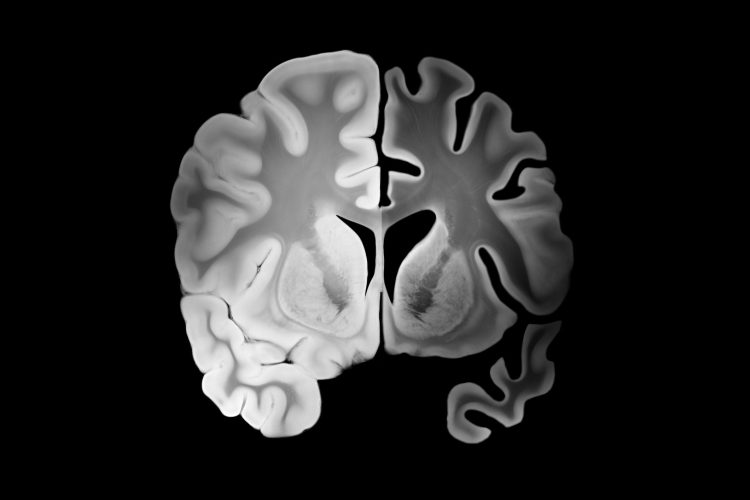

Πρόκειται για μονοκλωνικό αντίσωμα, το οποίο συνδέεται με το β-αμυλοειδές του εγκεφάλου και οδηγεί σε σημαντική μείωση του φορτίου των αμυλοειδικών πλακών στον εγκέφαλο των ασθενών με νόσο Alzheimer, με συνέπεια τη σημαντική επιβράδυνση στην κλινική επιδείνωση της νόσου.

Πρόκειται για φάρμακο πολύ υψηλού κόστους και η χορήγηση θα γίνεται ενδοφλέβια στο νοσοκομείο και θα εγκρίνεται ονομαστικά για κάθε ασθενή που πληροί τα κριτήρια να το πάρει. Σήμερα, στην Κρήτη, ο αριθμός των ασθενών ξεπερνούν τις 12.000 και οι μισοί από αυτούς ζουν στο ν. Ηρακλείου. Ο κ. Ζαγανάς σημειώνει ότι, σύμφωνα με έρευνα, σήμερα, στο νησί, 1 στους 10 άνω των 60 πάσχει από άνοια.

Σύμφωνα με τη νευρολόγο δρ Παρασκευή Σακκά, «μείζονα εξέλιξη στη θεραπευτική του νοσήματος αυτού απετέλεσε η έγκριση του νέου φαρμάκου από τον FDA, τον Ιούλιο του 2023, για τη θεραπεία της ήπιας νοητικής διαταραχής και της ήπιας άνοιας που οφείλεται στη νόσο Alzheimer».

Όπως επισημαίνει: «Ενδείκνυται για επιλεγμένους ασθενείς με επιβεβαιωμένη πρώιμη νόσο Alzheimer, η χορήγησή του δε απαιτεί τεκμηριωμένη διάγνωση με βιοδείκτες (παθολογικές πρωτεΐνες στο εγκεφαλονωτιαίο υγρό ή PΕΤ αμυλοειδούς). Χορηγείται 2 φορές τον μήνα ενδοφλεβίως με νοσηλεία στο νοσοκομείο και η χρήση του, όπως προκύπτει από τα δεδομένα των κλινικών μελετών, απαιτεί την αυστηρή τήρηση πρωτοκόλλου παρακολούθησης και διαχείρισης σοβαρών ανεπιθύμητων ενεργειών.

Η νευρολόγος υπογραμμίζει: «Το μονοκλωνικό αντίσωμα σίγουρα δεν αποτελεί το φάρμακο που έφερε το θαύμα ή τη ριζική θεραπεία για τη νόσο Alzheimer, όπως περιεγράφηκε σε κάποια ΜΜΕ ή έγινε λανθασμένα αντιληπτό από κάποιες οικογένειες ασθενών».